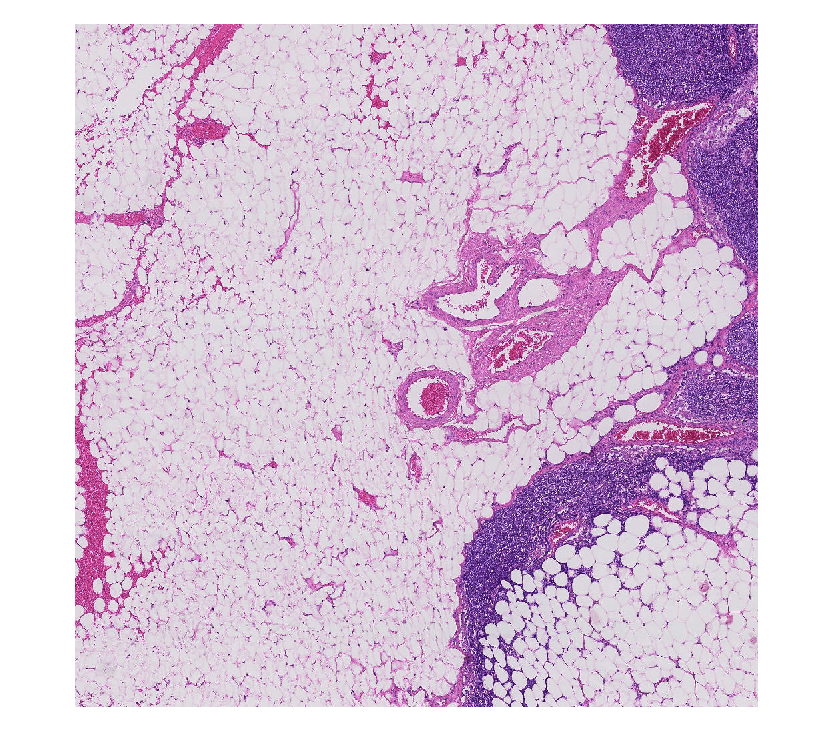

bim = blockedImage('tumor_091R.tif');

imshow(block)

Figure contains an axes object. The axes object contains an object of type image.